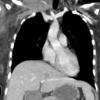

Lymphoma  coronal CT

Date: 07/27/2013

Views: 1865